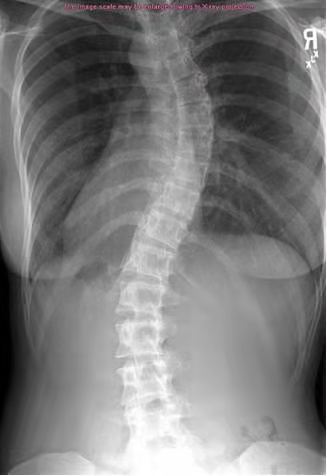

脊椎侧弯指的是脊椎不正常地侧向弯曲。脊椎本来应该呈一字线,却弯向左边或右边,看起来就像个“C”或“S”型。大部分的脊椎侧弯均属轻微,然而严重侧弯会引起心肺问题,并造成身体外观畸形。大多数情况下,脊椎在上背部向右弯曲,而在下背部向左弯曲,脊椎弯曲,会导致肋骨在一侧向前推动,因此,如果脊椎向右弯曲,则右侧肋骨将向后凸出,这会导致肋骨之间的肌肉过度伸展,而左肋骨会受压。

更简单的方法就是进行X光检查,大部分侧弯都属于轻微弯曲,不需要接受治疗,如果曲率到45度或更高,医生通常会建议手术。